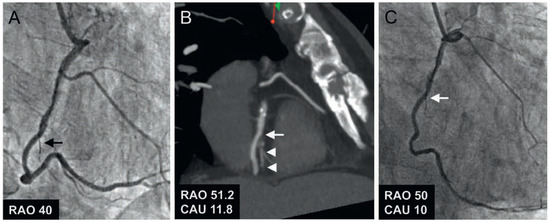

Aims: To investigate the feasibility and safety of TAVI without prior invasive assessment. Methods and Results: A total of 489 patients underwent TAVI for treatment of severe aortic stenosis between July 2007 and April 2012 and were included in a pro...